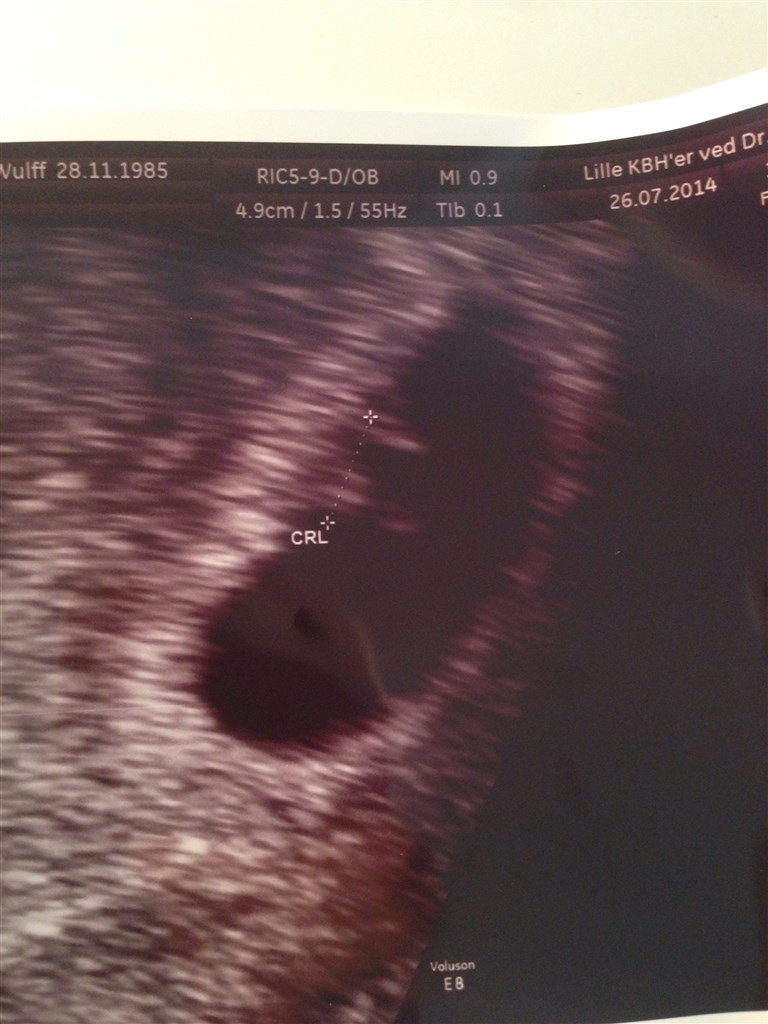

Så har jeg været til scanning. I følge mine egne beregninger er jeg 6+3, men lægen der scannede mig målte den lille til at jeg var ca. 6+1.

Den sad hvor den skulle og vi kunne se og høre et lille fint hjerte blinke.